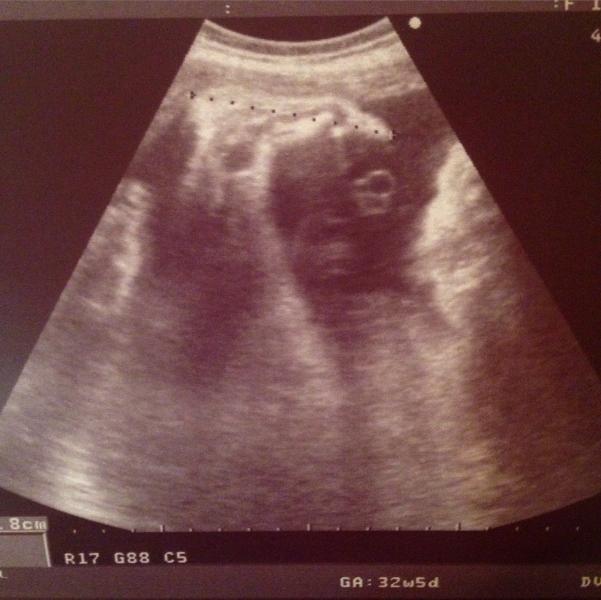

Сегодня наконец-таки состоялась наша встреча с карапузом😍 Наша последняя такая встреча... Как же я ждала её, так соскучилась - нет слов😇 Лежим мы по деловому! Одна ручка за головой... Как будто загорает на пляже😎✌Показали личико - такой смешной😊 Красавчик😍 У меня всё узи глаза слезились, потому что это последний раз, когда мы так встречаемся. В следующий раз я уже скажу: "Привет, я твоя мама! Добро пожаловать в этот Мир!"😊 А на фото ножка...👣 Зацелую, когда увидимся!💋💋💋